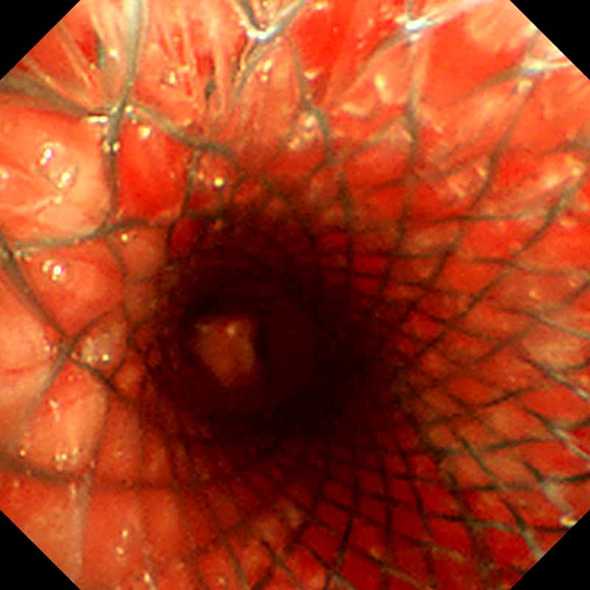

支架植入后气管通畅

放置L型支架的全影完美图像

5月22日13:30姜云飞、牟海军在重症医学科医护团队的护航下,腔镜中心副主任护师李晶、护师谭丽丽的配合下,为王先生成功实施了L型镍钛合金气管支架植入术,手术在局麻下进行,全程用时30分钟。术后王先生呼吸困难立即改善,血氧饱和度100%。他兴奋地要求自己走回病房,享受一下久违的顺畅呼吸。5月25日复查支架位置良好,完全覆盖病变,狭窄段彻底通畅,王先生也顺利地转到放疗科继续食管癌的治疗。